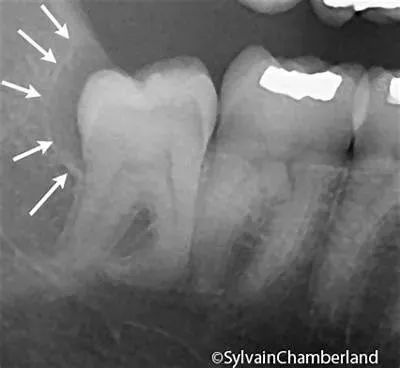

智齿刚萌出时的牙周膜时牙周膜对智齿“抓”得还没那么牢固,再加上周围骨质较松,拔牙时骨阻力较少。欣赏一下整齐的、牙根尚未发育完全的智齿↓

医生拔得轻松,你也恢复得更快。18岁的牙根 vs 28岁的牙根↓